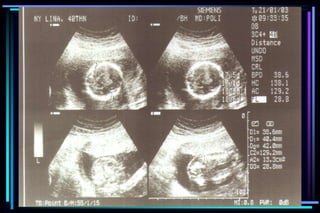

 Biparietal diameter (BPD)

 Head Circumference (HC)

 Abdominal Circumference (AC)

Ultrasound parameter Accuracy

 Gestational sac diameter + 7 days

 Crown Rump Length + 3-5 days

 BPD second trimester + 1 to 1.5 weeks

 BPD third trimester + 2 to 4 weeks

 FL second trimester + 1 to 1.5 weeks

 FL third trimester + 3 to 3.5 weeks

 Multiple parameter (2nd trimester) + 1.5 weeks

 Multiple parameter (3rd trimester) + 2.5 weeks